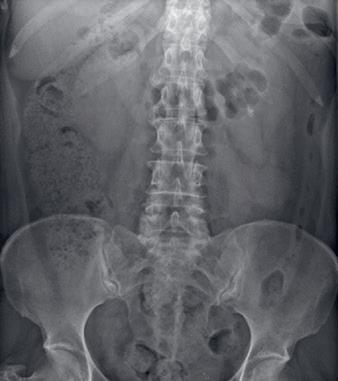

calamiteiten (%) onderzoek-diagnostiek medicatieverpleegkundigezorg operatiefproces

Bij de IGJ worden calamiteiten gemeld vanuit verschillende zorgaanbieders. In de medisch specialistische zorg, met onder andere ziekenhuizen en particuliere klinieken, zijn in 2017 1035 calamiteiten en in 2020 880 calamiteiten gemeld. De meeste calamiteiten worden gemeld in de categorie onderzoek/diagnostiek. Hier worden calamiteiten onderverdeeld die betrekking hebben op:

– resultaten van een onderzoek die worden verwisseld met die van een andere patiënt (figuur 1).

50 45 40 35 30 25 20 15 10 5 0 2017 2018 2019

Figuur 1 Aantal calamiteiten in de medisch specialistische zorg in percentages.